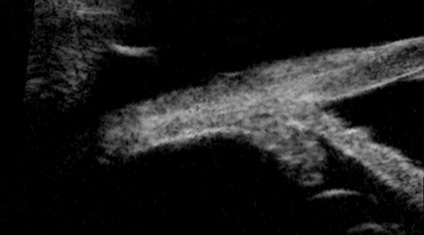

Pre MicroPulse®

Post MicroPulse®